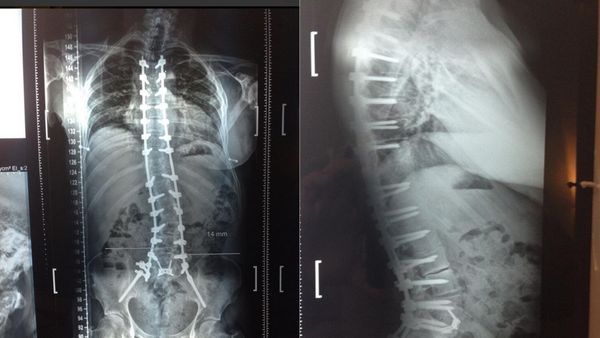

Radiografía de la columna de Ricardo Fort

La última intervención a la que se sometió fue en septiembre: le implantaron 16 tornillos de itanio en la columna, más dos varillas para apuntalarla, y anillos de metal para separar vértebrars y evitar el desgaste de los discos. Aquella cirugía llevó nueve horas, y aunque todo salió bien los problemas no tardaron en llegar luego de que su organismo rechazara los cuerpos extraños, ocasionándole aún más problemas.